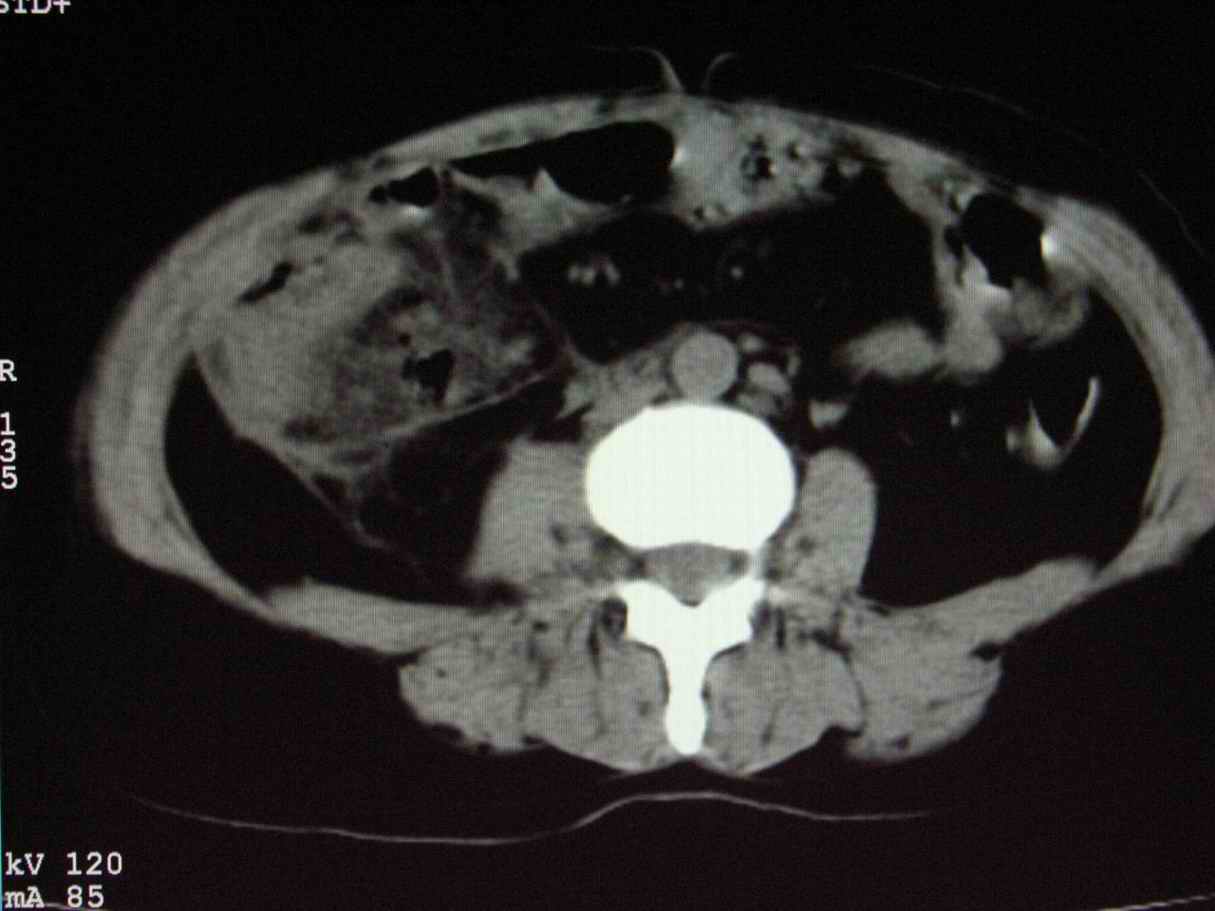

男;67岁,腹胀,腹痛,便血半年;钡餐透视发现右下腹部占位性病变

ct表现;病灶成环状软组织肿块,表现为不对称的肠壁增厚;肠腔变型.

升结肠肠壁不均匀增厚,肠腔变形,支持结肠癌.